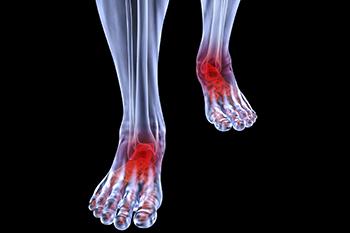

Conditions affecting the feet due to complications with arthritis can take many forms, including osteoarthritis, rheumatoid arthritis, gout, psoriatic arthritis, and ankylosing spondylitis. Osteoarthritis typically affects the joint connecting your big toe to your foot, though it can also be found in the midfoot or ankle region. Unlike osteoarthritis, rheumatoid arthritis typically affects both feet and deals with the same joints on each foot. Gout, which normally affects the big toe, is comprised of needle-like crystals that trigger inflammation in the joints. Psoriatic arthritis causes sausage-like swelling in the toes. Lastly, ankylosing spondylitis can lead to plantar fasciitis and pain at the Achilles tendon.